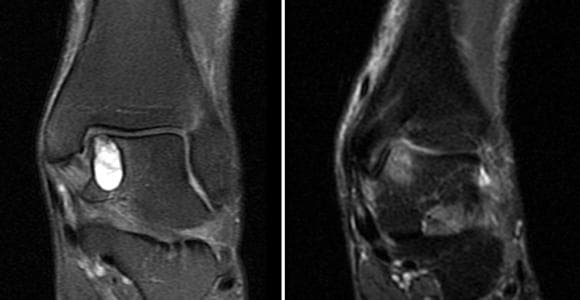

Mozaikoplasti Nedir?

Mozaikoplasti, Eklemin yük taşımayan bölgesinden 6-8 mm çapında ve 15 mm boyunda kıkırdak ve kemikten oluşan silindirik...